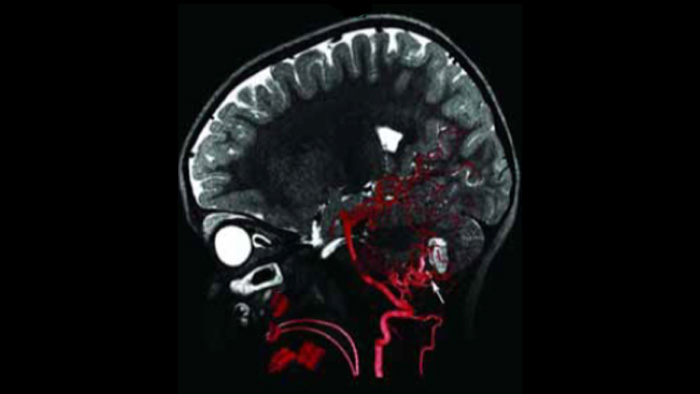

Visualice los límites de la lesión y la vascularización correspondiente

MR-CT Roadmap

MR-CT Roadmap ofrece la posibilidad de superponer una angiografía de SmartCT Angio o angiografía por RM previamente adquiridas con fluoroscopia en tiempo real para visualizar los límites de las lesiones y la vascularización correspondiente para la evaluación de riesgos. La reutilización de datos adquiridos previamente le ayuda a administrar la dosis de rayos X y el contraste.